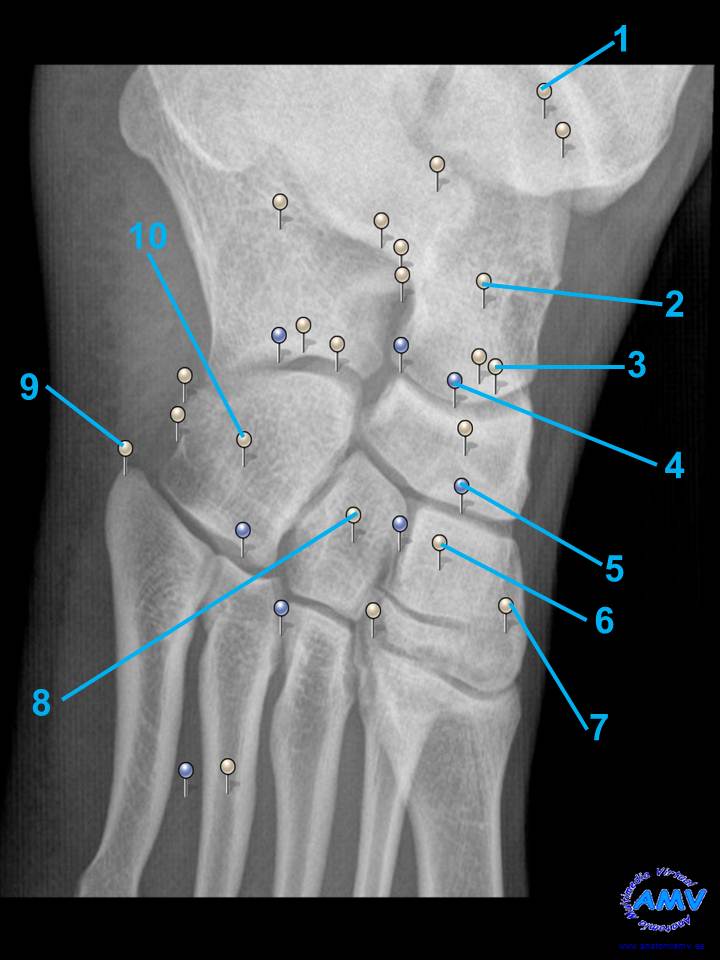

rx_mi_11.jpgIndique que estructura se señala con el número correspondiente:

El nº 1 señala .

El nº 2 señala .

El nº 3 señala .

El nº 4 señala .

El nº 5 señala .

El nº 6 señala .

El nº 7 señala .

El nº 8 señala .

El nº 9 señala .

El nº 10 señala .